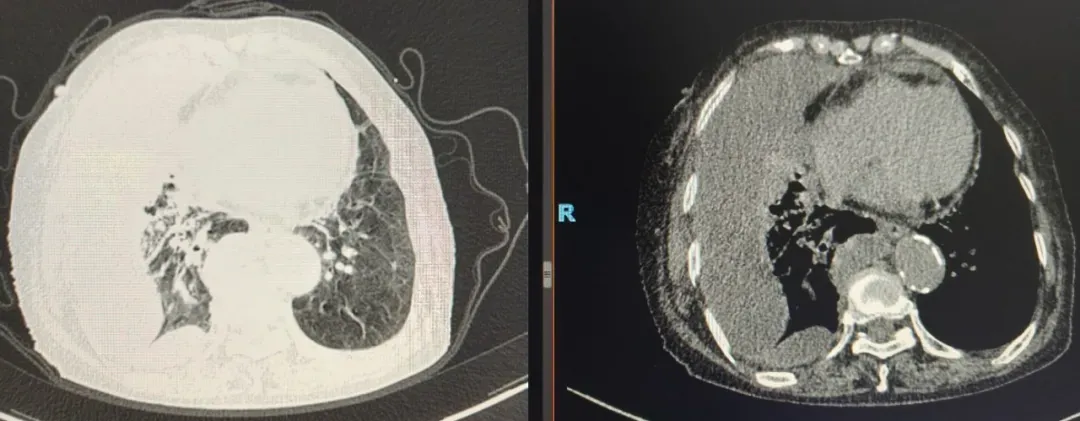

该患者因胸闷气短两月余、加重一周入院,本身患有心脏基础疾病及其他慢性基础病,经心电图、心脏超声等检查排除心脏器质性病变主导因素后,心病科第一时间邀请肺病科会诊。结合胸部影像学检查结果,专家团队判断患者症状由包裹性胸腔积液引发,需要通过胸膜活检明确积液性质,患者随即转入肺病科进一步治疗。

术后第三天